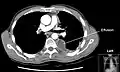

Op een longfoto is pleuravocht zichtbaar als een wit gedeelte op de longfoto.[4] Op een normale thorax foto is de ruimte tussen de viscerale pleura en de pariëtale pleura niet zichtbaar. Wanneer er pleuravocht aanwezig is, is deze ruimte wel zichtbaar. De densiteit van pleuravocht is ongeveer gelijk aan die van water, hierdoor is dit witter op een longfoto in vergelijking met de rest van de long (die meer de densiteit van lucht heeft). Door de hogere densiteit zal pleuravocht zich altijd bevinden op het laagste punt van de thoraxholte en is er een bij horizontale vloeistofspiegel (meniscus).[5] Een longfoto in zijligging (op de zijde waar het pleuravocht zich bevindt) is sensitiever voor pleuravocht. Dit wordt een "decubitus opname" genoemd, bij deze opname wordt een hoeveelheid van 50 ml of meer pleuravocht zichtbaar. Een CT-scan van de borstkas is het meest nauwkeurig voor het bepalen van de aanwezigheid van pleuravocht, maar ook de hoeveelheid en kenmerken van het pleuravocht. Ook echografie kan gebruikt worden om pleuravocht aan te tonen.[6]

CT-scan van de borstholte met linkszijdig pleuravocht. Het pleuravocht bevindt zich meestal in het laagste gedeelte van de thorax, de rugzijde omdat de patiënt in rugligging ligt.- Echografischbeeld van een long met pleuravocht.